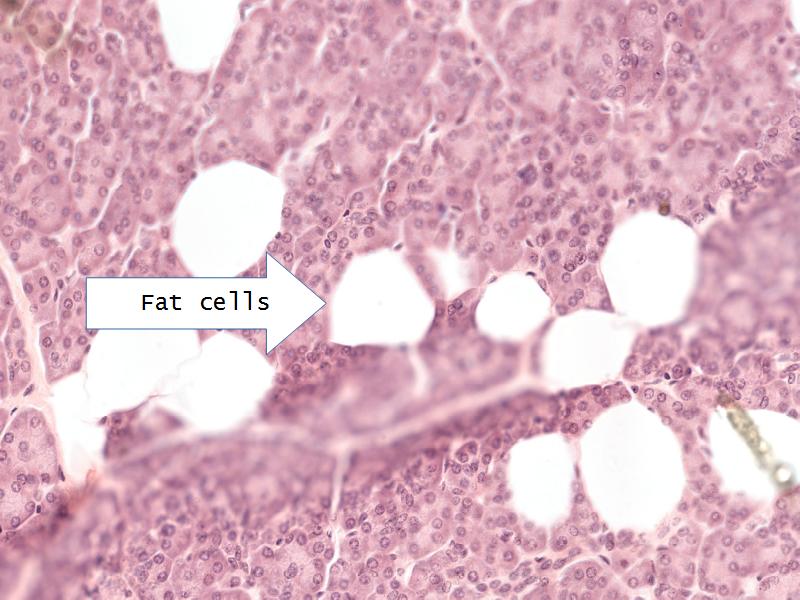

- Pancreas

- C3: Pancreas

- C3: Pancreas = glucagon, insulin, somatostatin, pancreatic polypeptide

- F4: Alpha cells = pancreas

- Slide 50: Pancreas